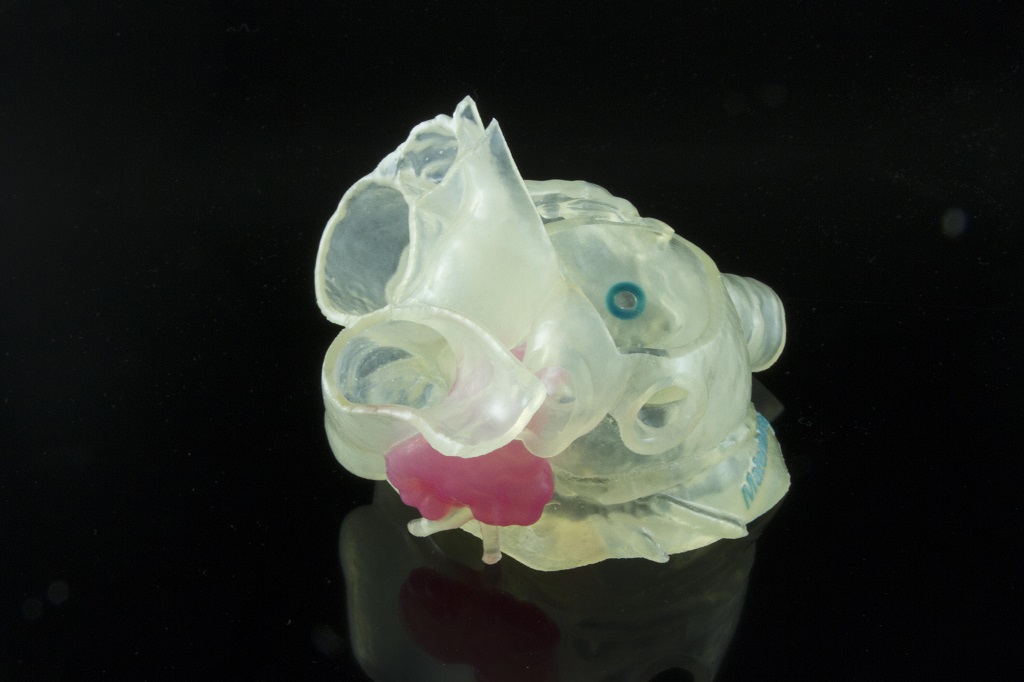

Materialise Enlightens Medical Care With FDA-Approved Cardiovascular Software

Materialise has received FDA clearance for its cardiovascular planning software.

Materialise Mimics inPrint Certification Program Clears Ultimaker and Formlabs for Medical 3D Printing

Materialise’s announcement today of FDA-cleared medical model 3D printing encompasses vat polymerization and material extrusion technologies in addition to PolyJet.

FDA-Cleared Medical 3D Printing with Stratasys and Materialise

3D printing medical models offers benefits to patients and those providing their care with highly accurate patient-specific anatomies able to be held, examined, and practiced on.